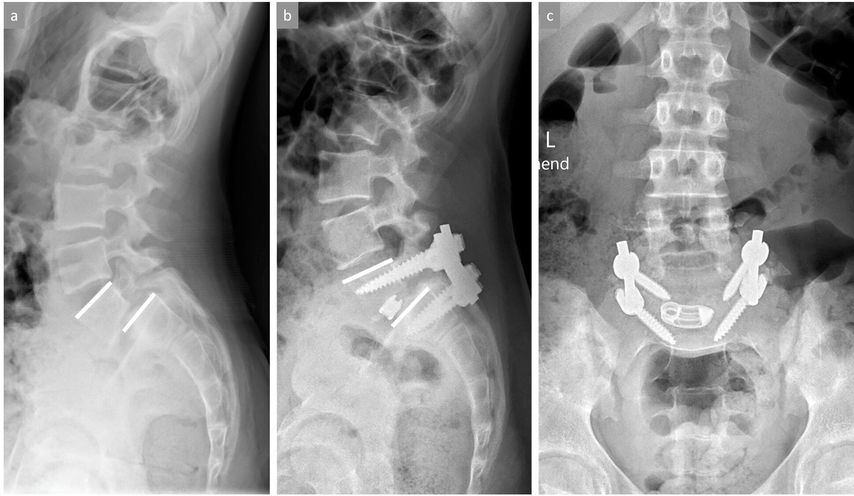

Wenn eine knöcherne Ausheilung der Spondylolyse bei symptomatischen Patienten sehr unwahrscheinlich ist (radiologisch sklerosierte, abgerundete Frakturränder des Pars-Defekts) und insbesondere bei gleichzeitigem Vorliegen einer leichtgradigen Spondylolisthese sind die Ergebnisse konservativer Massnahmen deutlich seltener nachhaltig erfolgreich und ein früheres operatives Vorgehen sollte zumindest angesprochen werden. Bei objektivierbarer Progression der Spondylolisthese und/oder neurologischen Symptomen ist die Indikation für eine operative Stabilisierung grundsätzlich gegeben. Bei fehlenden knöchern-dysplastischen Veränderungen und noch intakter Bandscheibe zwischen den betroffenen Wirbeln (i.d.R. L5/S1) kann ein sogenannter «direct pars repair» durchgeführt werden. Hierbei wird nach Resektion einer allfälligen Pseudarthrose der Defekt mit einer Schraube durch die Pars interarticularis direkt verschraubt oder alternativ ein Konstrukt aus Pedikelschraube und Laminahaken frakturüberbrückend bilateral eingebracht (Abb. 4). Wenn die Betroffenen nicht für einen «direct pars repair» qualifizieren, wird eine (instrumentierte) posterolaterale Fusion der betroffenen Segmente durchgeführt.

Abb. 4: Bild (a) zeigt ein stehendes seitliches Röntgenbild der LWS mit objektivierbarer isthmischer Spondylolyse (Pfeil) im Bereich der Pars interarticularis von LWK5 mit belgeitender leichtgradiger Spondylolisthese LWK5/SWK1. Bilder (b) und (c) zeigen die Situation nach erfolgter Operation mittels «direct pars repair», bei welcher der Pars-Defekt auf beiden Seiten durch ein Pedikelschrauben-Laminahaken-Konstrukt nach Resektion der Pseudarthrosezone überbrückt wird. Der weisse Pfeil im kleinen Bildausschnitt von Bild (b) zeigt eine vollständige knöcherne Ausheilung des ehemaligen Pars-Defekts